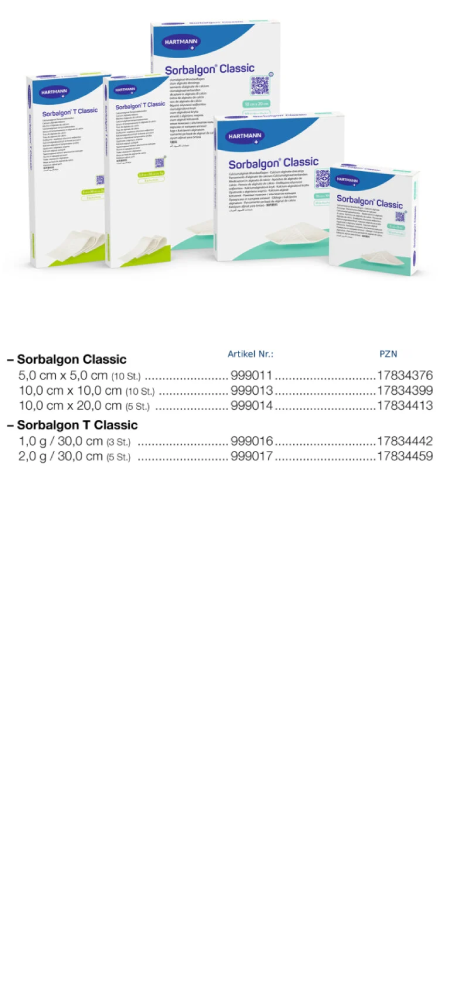

Sorbalgon Classic

Sorbalgon T Classic